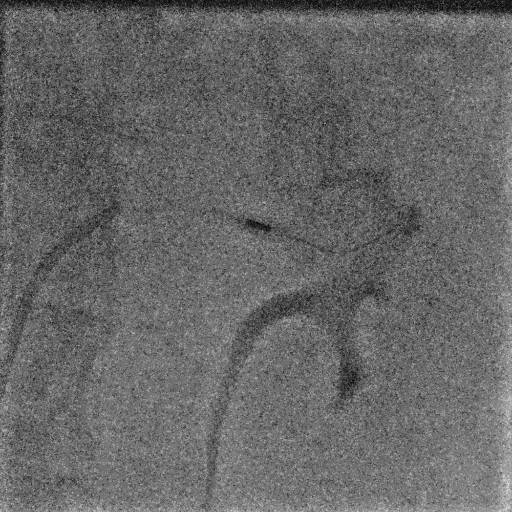

手術(shù)中,團(tuán)隊(duì)通過(guò)穿刺右側(cè)股動(dòng)脈,置入動(dòng)脈鞘和導(dǎo)管,對(duì)左右腎動(dòng)脈進(jìn)行造影評(píng)估后,使用Hawk Sonic超聲消融導(dǎo)管對(duì)腎動(dòng)脈分支及主干進(jìn)行消融治療。

術(shù)后患者血壓顯著下降,復(fù)測(cè)血壓149/72mmHg;手術(shù)次日血壓降至122/66mmHg,且術(shù)后2個(gè)月未發(fā)生任何不良事件,復(fù)查腎動(dòng)脈CTA未見(jiàn)狹窄等異常。

▲左側(cè)腎動(dòng)脈主干超聲消融